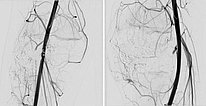

Die digitale Subtraktionsangiographie (DSA) des Knies (links a.-p. Projektion, links seitliche Projektion) zeigt eine AVM mit einem eher kugeligen, aneurysmatischen Nidus sowie einen weiteren Nidus intraossär im lateralen Tibiaplateau. Dieser sehr kugelige, aneurysmatische Nidus zusammen mit der schmerzhaften, progredienten Raumforderung lässt an ein PTEN-Hamartom denken.

Nach erfolgreicher Embolisation der beiden AVM-Nidusanteile zeigt sich in den Röntgenübersichtsbildern (links a.-p., rechts seitliche Projektion) ein vollständiger Ausguss der beiden Anteile durch das Embolisat, der sogenannte Cast. Dieser besteht aus Ethylen-Vinyl-Alkohol-Kopolymer.

In der Kontroll-DSA (links a.-p., rechts seitlich) nach Embolisation mit Ethylen-Vinyl-Alkohol-Kopolymer zeigt sich auch in einer langen Serie keinerlei Perfusion mehr in der Angiographie. Die AVM gilt als verschlossen.

In der erneuten DSA 4 Monate nach der vorherigen Embolisation (links a.-p., rechts seitlich) zeigt sich ein frühes, umschriebenes Rezidiv. Gerade bei AVMs im Zusammenhang mit einem PTEN-Hamartom-Syndrom müssen die Patienten enge Nachsorgeintervalle einhalten da gerade diese AVMs eine hohe Rezidivneigung aufweisen.